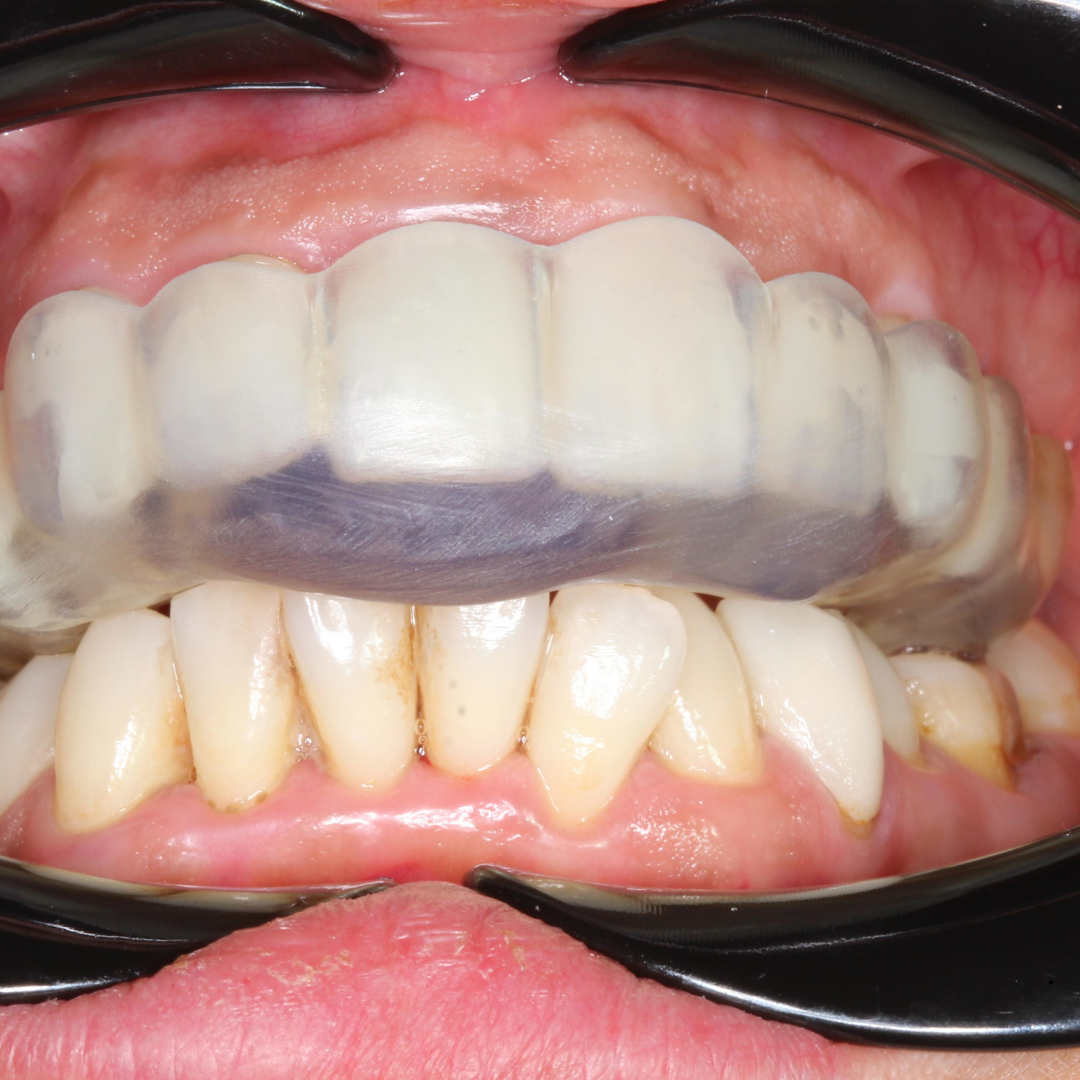

TMJ Orthotic Treatment in Turkey: Relieve Pain and Restore Harmony Temporomandibular Joint (TMJ) disorders can cause persistent jaw pain, headaches,

TMJ Orthotic Treatment Read Post »